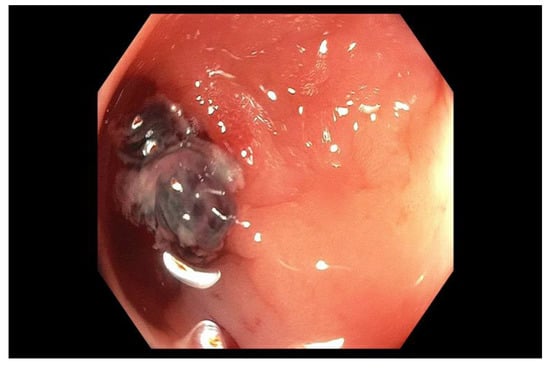

2.5. Endoscopic Therapy for Bleeding Peptic Ulcer Disease

2.6. Endoscopic Therapy for Other Non-Variceal Causes of Upper GI Bleeding